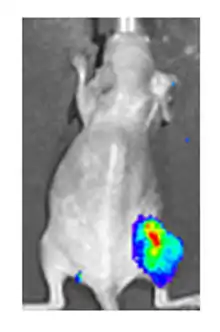

ويمكن القيام بذلك عن طريق تزويد الفيروس ب "الجينات المراسلة" التي لا تتواجد عادة في الجينوم الفيروسي، التي تعمل كعلامات ترميز بروتينية يمكن التعرف عليها بسهولة. أحد الأمثلة على هذه البروتينات هو GFP (بروتين الفلورسنت الأخضر) الذي، عند وجوده في الخلايا المصابة، سوف يسبب انبعاث الضوء الأخضر الفلورسنت عندما يتم تحفيزه بالضوء الأزرق. [70][71]ميزة هذه الطريقة هي أنه يمكن استخدامها على الخلايا الحية وفي المرضى الذين يعانون من إصابات سطحية، فإنها تتيح تأكيد سريع غير مخترق للعدوى الفيروسية.[72] مثال آخر على علامة مرئية مفيدة في الخلايا الحية هو لوسيفيراس، وهو إنزيم من اليراع الذي في وجود لوسيفيرين، يبعث ضوء يمكن اكتشافه بواسطة الكاميرات المتخصصة.[70]

إضافة الجين رابط يوديد الصوديوم (نيس) إلى الجينوم الفيروسي يؤدي بالخلايا السرطانية المصابة للتعبير عن رابط يوديد الصوديوم ويراكم الأيودين. عندما يقترن العلاج باليود المشع فإنه يسمح بالعلاج الإشعاعي المحلي للورم، كما يستخدم لعلاج سرطان الغدة الدرقية. ويمكن أيضا استخدام اليود المشع لتصوير النسخ الفيروسي داخل الجسم عن طريق استخدام كاميرا غاما. [70] استخدم هذا النهج بنجاح قبل ـ سريريًا مع الفيروس الغدي، وفيروس الحصبة وفيروس الوقس.[77][78][79]